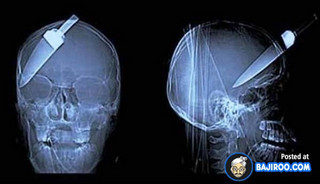

Ο,ΤΙ ΝΑ 'ΝΑΙ #ακτινογραφίες Παράξενα πράγματα που έχουν δείξει οι ακτινογραφίες Από δαχτυλίδια μέχρι πιρούνια και καρφιά - Δείτε τις φωτογραφίες 15·04·2016 11:08 1 σχόλια